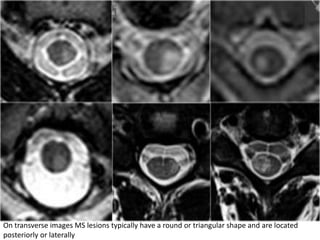

On transverse images MS lesions typically have a round or triangular shape and are located

posteriorly or laterally

So can we exclude MS if a lesion is located anteriorly?

Unfortunately not.

MS is the great mimicker and can also be located anteriorly like in this patient who has

a lesion in the typical location (blue arrow) but also a lesion ventrally in the cord (red

arrow).

This is uncommon, but we can not exclude MS.